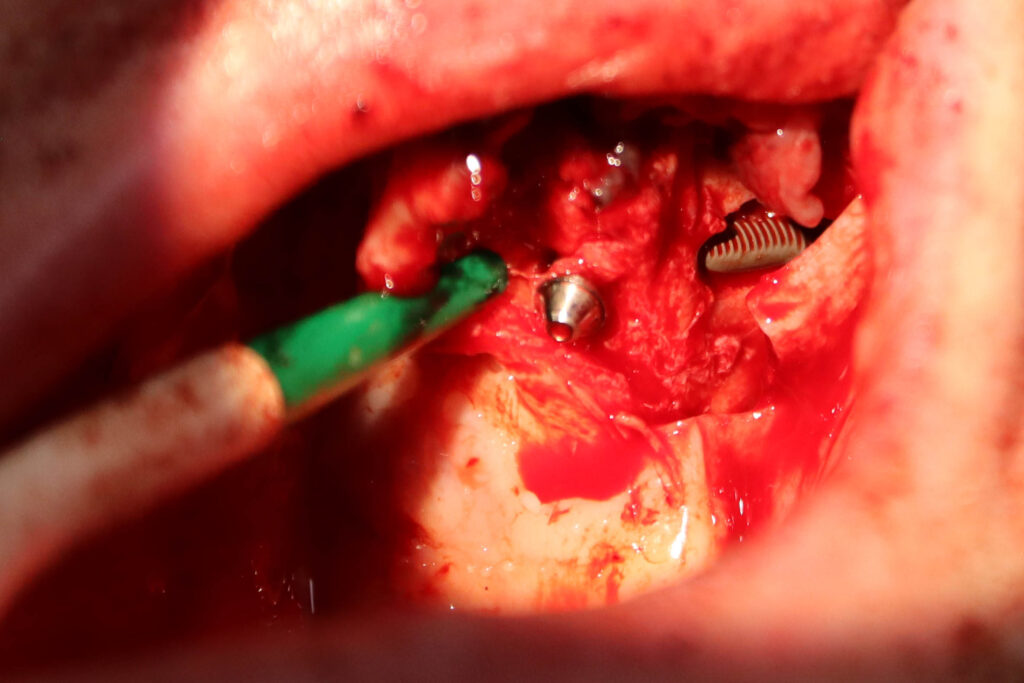

процесс имплантации

Это фото может содержать тяжелый для восприятия контент